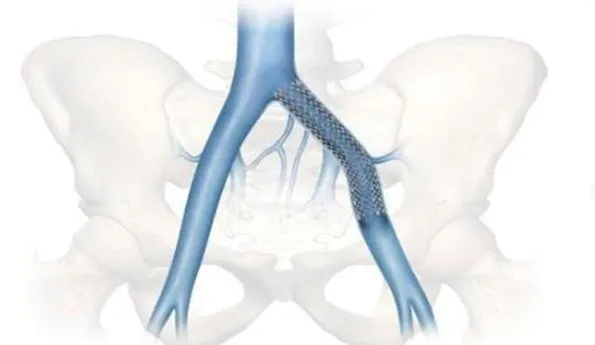

左侧髂总静脉内植入支架

左图:该病例双侧髂静脉系统完全闭塞,静脉引流是通过盆腔和脊柱周围广泛的静脉侧支网络;右图:显示的是植入的左侧与右侧髂静脉支架,下腔静脉内是从两侧髂静脉伸入的对吻支架。